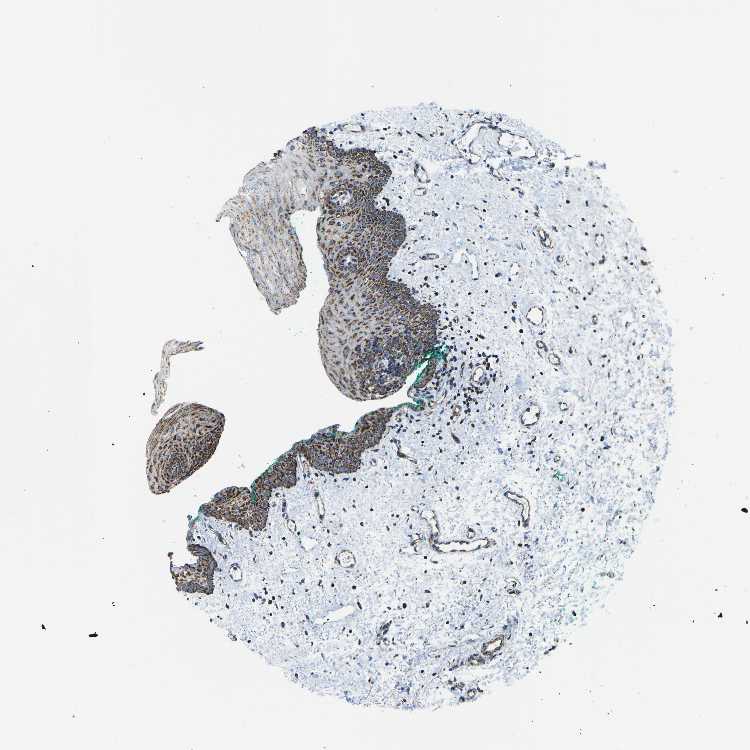

TISSUE PRIMARY DATA ORAL MUCOSA Show tissue menu

ORAL MUCOSA - Antibody stainingi

Antibody staining in the annotated cell types in the current human tissue is reported as not detected, low, medium, or high, based on conventional immunohistochemistry profiling in selected tissues. This score is based on the combination of the staining intensity and fraction of stained cells.

Each image is clickable and will lead to virtual microscopy that enables deeper exploration of all samples and also displays staining intensity scores, fraction scores and subcellular localization as well as patient and tissue information for each sample.

Antibody HPA051505Antibody HPA054758Antibody CAB016243

Squamous epithelial cells HighMediumHigh